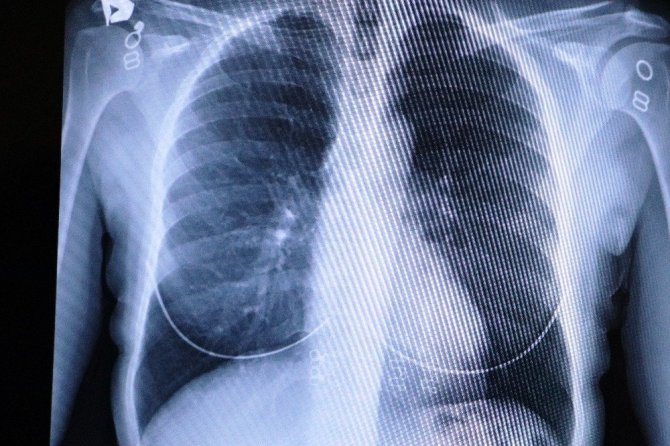

"Aşı olan ile olmayan evli çiftin akciğerlerindeki inanılmaz fark"

Bir evli çiftin akciğer filmlerini inceleyen Özkaya, "Size bir evli çiftin akciğer filmlerini göstermek istiyorum. İkisi de 50 yaşında. Çiftlerden biri sağlıkçı olduğu için aşılandı, diğeri ise aşı olmadı. Bu kadın hastamız kendisi sağlıkçı olduğu için Covid-19 pozitif olmasına rağmen akciğerlerinde hiçbir lezyon yok. Yine aynı yaştaki eşi aşı yapılmadığı için akciğerlerinde Covid-19 lezyonlarıyla uğraşıyoruz. İkisi de şu an korona servisinde yatıyor. Aşı olmayanın akciğerleri çok ciddi anlamda harap olmuşken aşı olan bir hastamızın testi pozitif olmasına rağmen akciğerleri tertemiz. Aile içi bulaş oldukça fazla. Özellikle bugün gelen ailenin akciğerlerine bakacak olursak, annenin ve babanın akciğerleri hafif tutulum sergilerken, 29 yaşındaki oğullarının akciğerlerinde aşırı bir tutulum var. Hasta profilleri biraz genç tarafa doğru kayıyor" şeklinde konuştu.